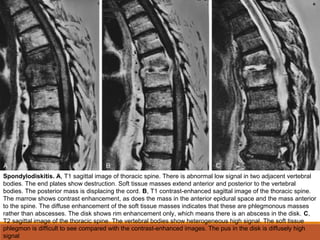

Spondylodiskitis. A, T1 sagittal image of thoracic spine. There is abnormal low signal in two adjacent vertebral

bodies. The end plates show destruction. Soft tissue masses extend anterior and posterior to the vertebral

bodies. The posterior mass is displacing the cord. B, T1 contrast-enhanced sagittal image of the thoracic spine.

The marrow shows contrast enhancement, as does the mass in the anterior epidural space and the mass anterior

to the spine. The diffuse enhancement of the soft tissue masses indicates that these are phlegmonous masses

rather than abscesses. The disk shows rim enhancement only, which means there is an abscess in the disk. C,

T2 sagittal image of the thoracic spine. The vertebral bodies show heterogeneous high signal. The soft tissue

phlegmon is difficult to see compared with the contrast-enhanced images. The pus in the disk is diffusely high

signal